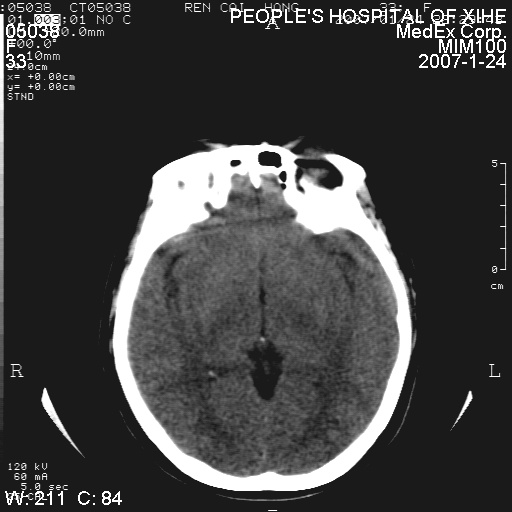

以下是引用卜一在2007-1-25 6:40:00的发言:[br]左侧额叶囊实混杂性病灶,多考虑胶质细胞瘤(ⅱ-ⅲ级),建议增强检查。[br]支持!

以下是引用wwwwtyy在2007-1-25 0:27:00的发言:[br]胶质瘤可能性大,不除外脑白质病变,建议强化

以下是引用守望可可西里在2007-1-25 0:13:00的发言:[br]左侧额叶囊实混杂性病灶,多考虑胶质细胞瘤(ⅱ-ⅲ级),建议增强检查!